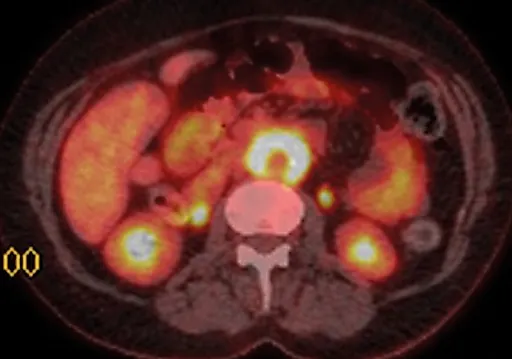

Инфекции мочевыводящих путей – состояние инфицирования мочевыводящего тракта микрофлорой, которая вызывает его воспаление.Различают инфекцию верхних (пиелонефрит) и нижних мочевых путей (цистит, простатит, уретрит) по наличию или отсутствию симптомов (симптоматическую или бессимптомную бак-териурию), по происхождению инфекции (внебольничную или нозокомиальную), осложненные и неосложненные.

Осложненные инфекции сопровождаются функциональными или анатомическими аномалиями верхних или нижних мочевых путей.